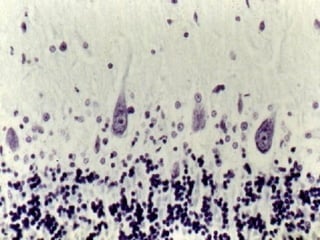

Neuronas sensitivas del asta posterior de la médula espinal .El perfil de los

somas es redondeado. Se observan los núcleos característicos y los grumos

de Nissl.

ASTA ANTERIOR

Asta anterior de la médula espinal. Observe el perfil anguloso de los somas

neuronales, los núcleos en “ojo de lechuza” y los grumos de Nissl. El detalle

del neurópilo es muy claro.